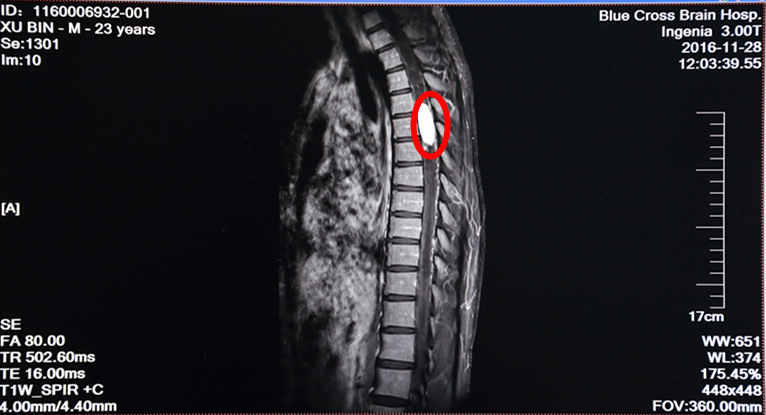

术前MRI增强扫描:红圈内白色物体为肿瘤,肿瘤两极广泛性脊髓空洞

病人徐某,23岁,双下肢失去知觉,行走不能1月半。在其他医院检查诊断为胸4--6段脊髓内血管母细胞瘤,属于最困难且风险很大的脊髓病变手术,该区域是椎管最狭窄,脊髓血供相对较丰富的部位。另外,病人第四脑室及右侧海马区颞角位置也发现有肿瘤,四脑室明显扩大、肿瘤明显压迫脑干。病家曾找我国最知名的一位脊髓外科专家看过,认为风险巨大,遂到我院寻求治疗,做增强MRI及DSA见肿瘤血供极其丰富,椎管内几乎仅见肿瘤而看不见正常的脊髓组织结构。